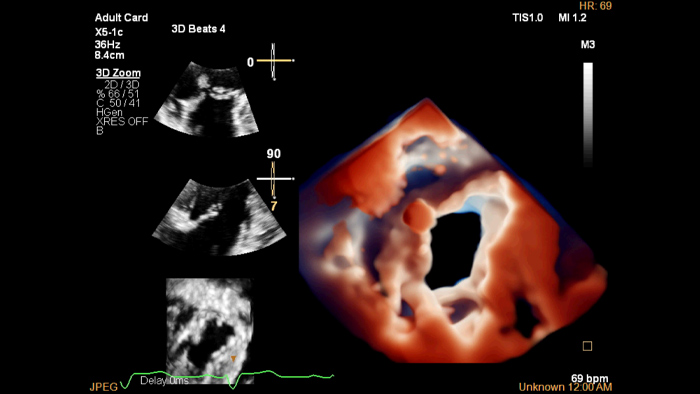

EPIQ CVx

La solution d’échocardiologie dédiée EPIQ CVx offre des fonctionnalités améliorées. Elle vous permet de dispenser des soins de qualité grâce à une puissance de traitement augmentée, une imagerie de qualité avec des détails plus nets & et plus précis et une optimisation de l’efficacité des examens, complétées par les fonctionnalités de quantification éprouvées et fiables d’Ultrasound Workspace.